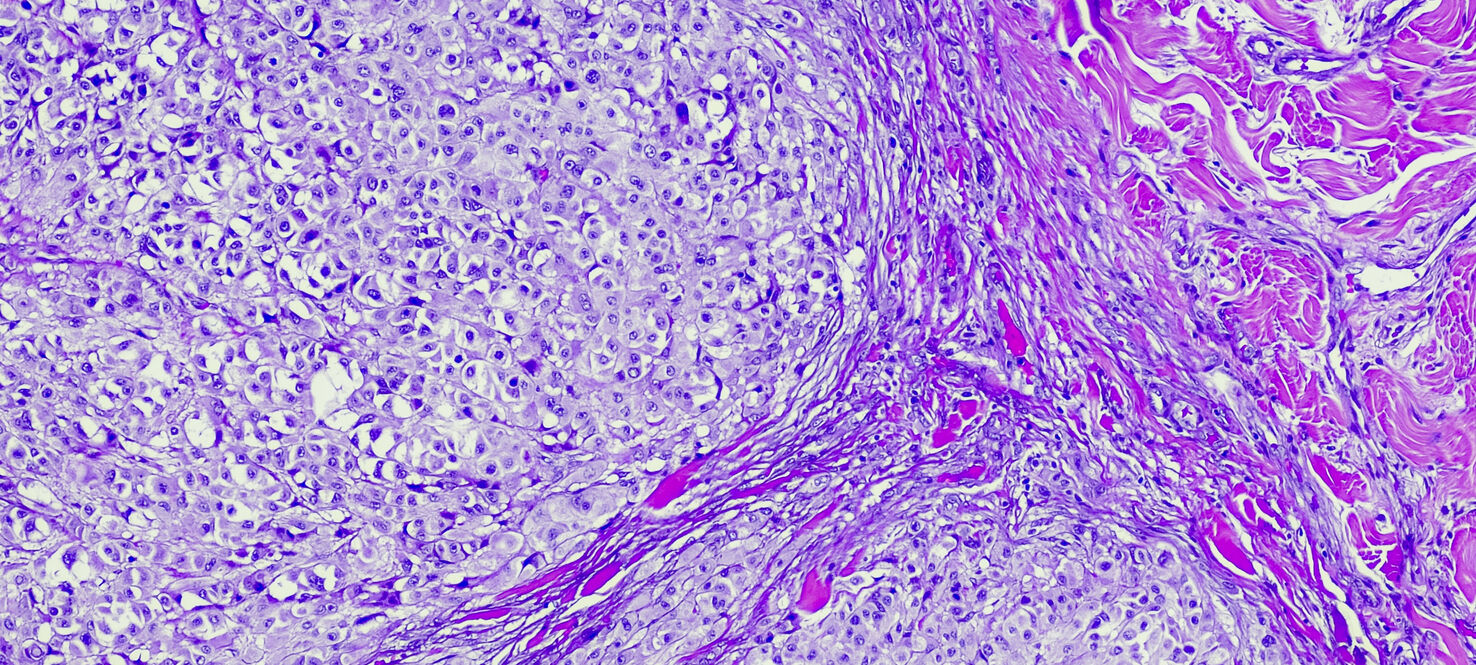

Tumor-infiltrating lymphocyte (TIL) therapy is a type of cellular immunotherapy in which a patient’s own cells are used to destroy tumor-based cancers.

During the treatment, immune cells are extracted from the patient’s tumor, multiplied in the lab and then infused back into the patient where they seek out and attack cancer cells.